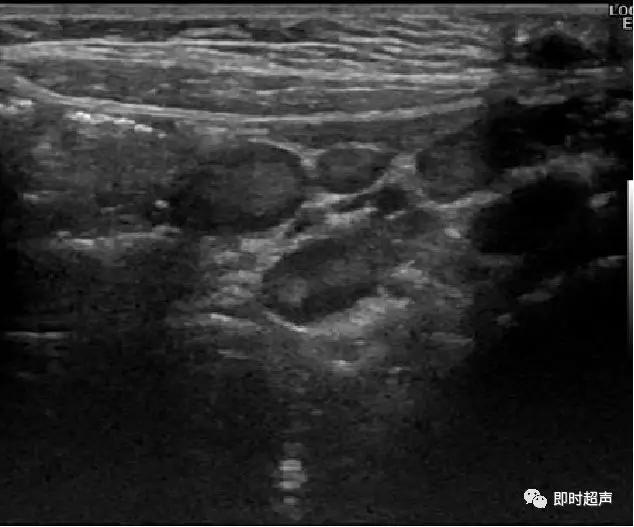

肠套叠超声表现

短轴切面同心圆征

长轴切面套筒征、短轴切面同心圆征

超声表现:

右中、下腹成串圆形或椭圆形低回声团

边界清,内部回声均匀,前后径>1cm

CDFI:分支状血流信号